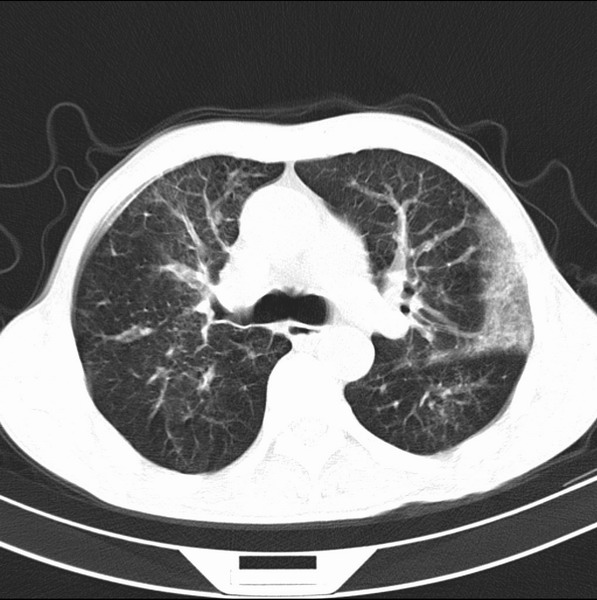

标题: CT19600:能否诊断为转移?

女、55

3年前盲肠癌、一年半前诊断膀胱癌,现在呼吸困难,临床考虑为肺转移

请问胸部ct如何诊断?能否排除淋巴管炎,纵隔窗没有问题。

考虑间质性病变,癌性淋巴管炎可能.

转移,癌性淋巴管炎。

建议抗炎后复查,不除外癌性淋巴管炎。

炎性并间质纤维化,请询问病史,如用过平阳霉素或其他化疗药.可能为药物引起的间质纤维化.